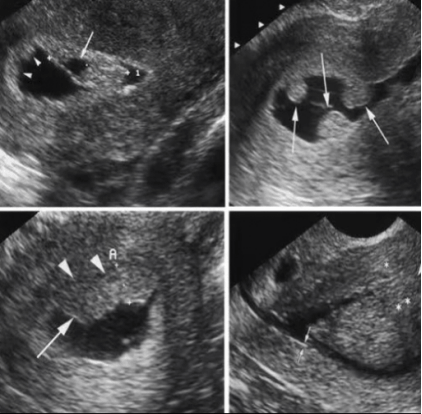

病例再现 / 01

二维超声显示肌瘤大部分位于肌壁间而不是宫腔内

宫腔水造影+三维超声显示肌瘤大部分凸向宫腔,仅有少部分位于肌壁间,二维超声不易观察到的宫腔粘连清晰可见。